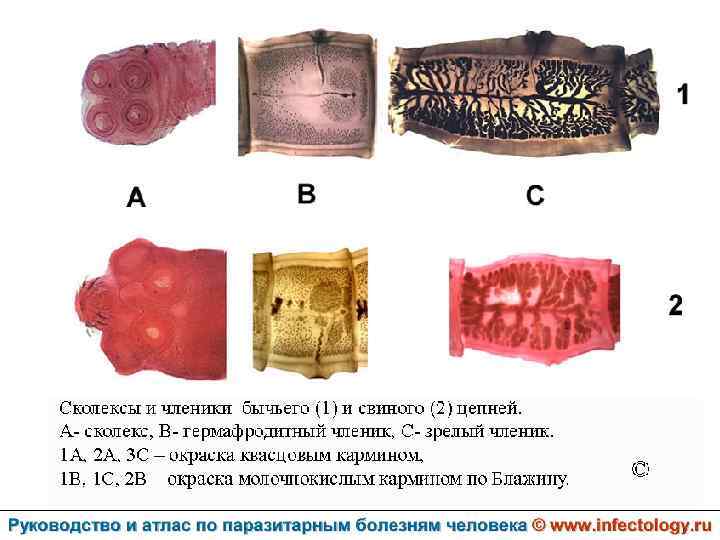

Тениаринхоз (шифр по МКБ 10 - B 68. 1) – антропонозный биогельминтоз с хроническим течением, характеризующийся преимущественно желудочно– кишечными расстройствами.

Тениоз (шифр по МКБ 10 - B 68. 0) – антропонозный биогельминтоз, одним из основных клинических проявлений которого является нарушение функций желудочно– кишечного тракта.